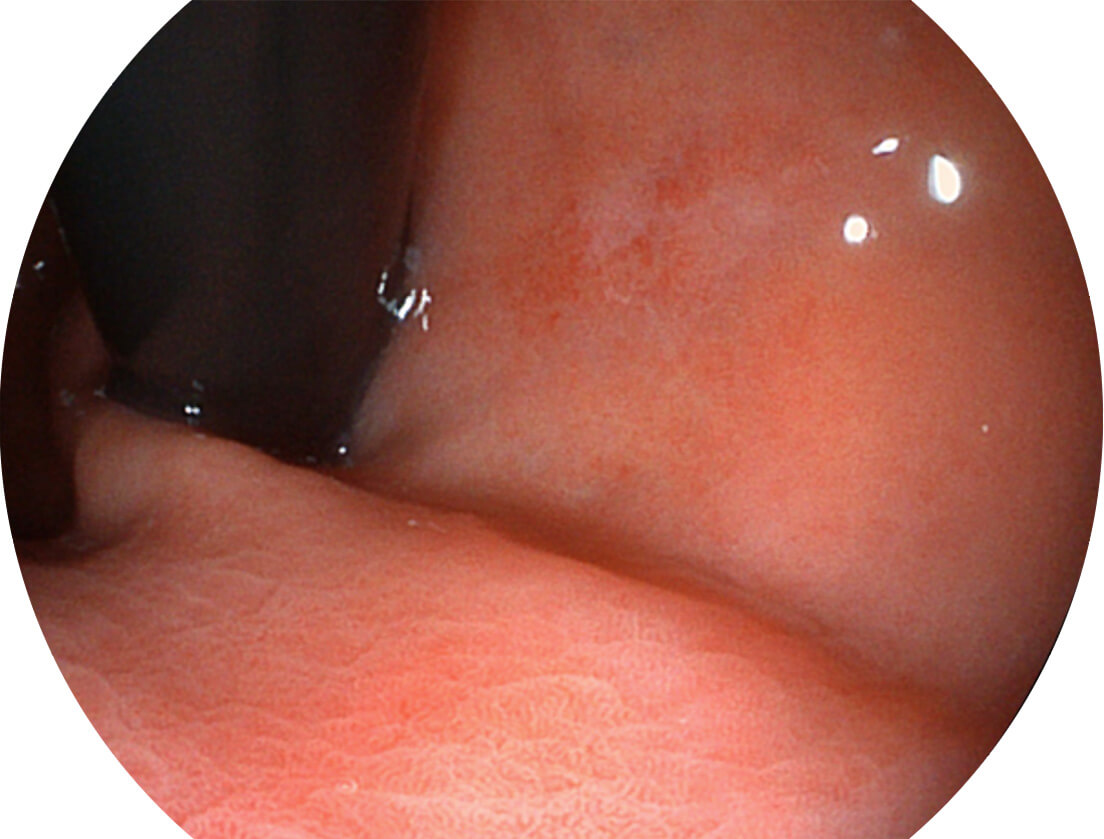

白光图像

SFI图像